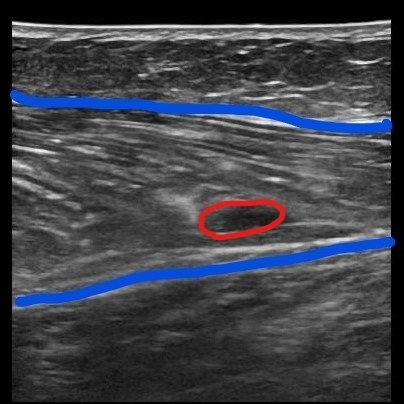

超音波診断装置を用い筋組織に炎症、損傷が生じているか画像所見を用い診断しています。下の画像はふくらはぎを撮像したものです。左は正常な筋繊維です。右は肉離れの状態です。

筋損傷を起こすと筋配列が崩れます。また、赤く囲った部分に炎症による血腫が見えます。